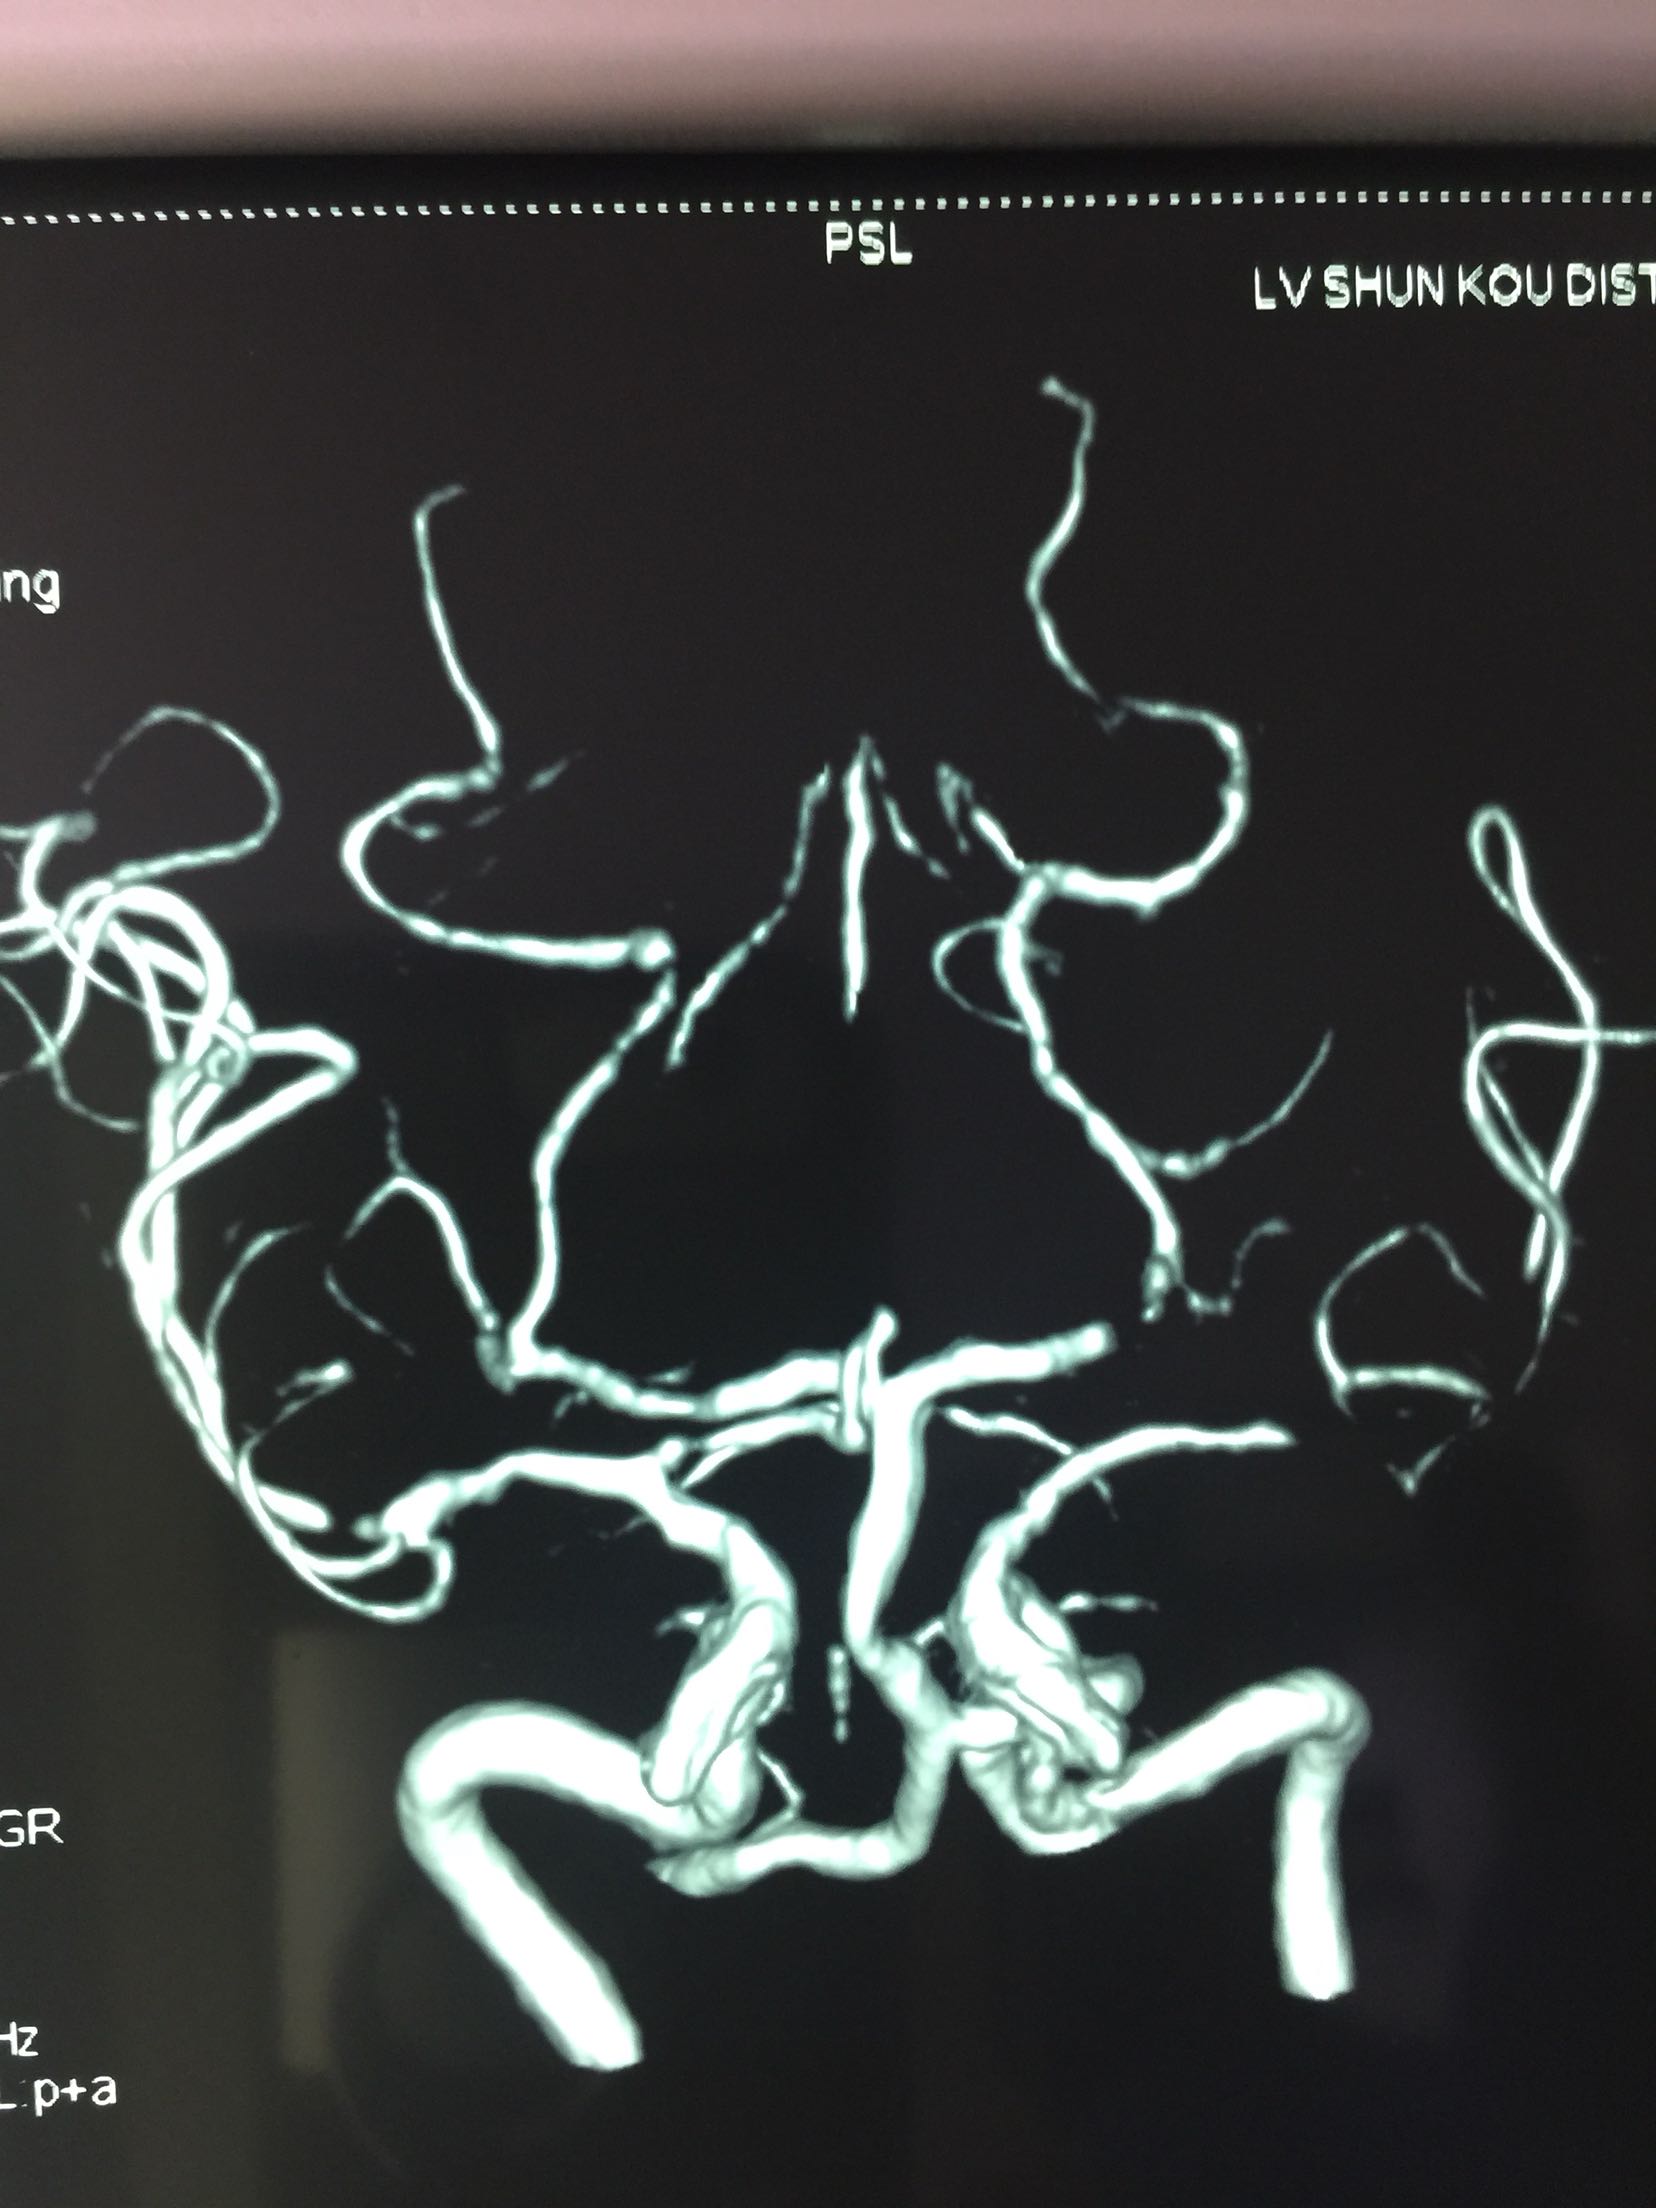

随访及预防:66岁男患,首先TIA发作,之后脑梗死,MRA可见左侧大脑中动脉狭窄,目前双抗血小板,联合大剂量他汀,未再发作。